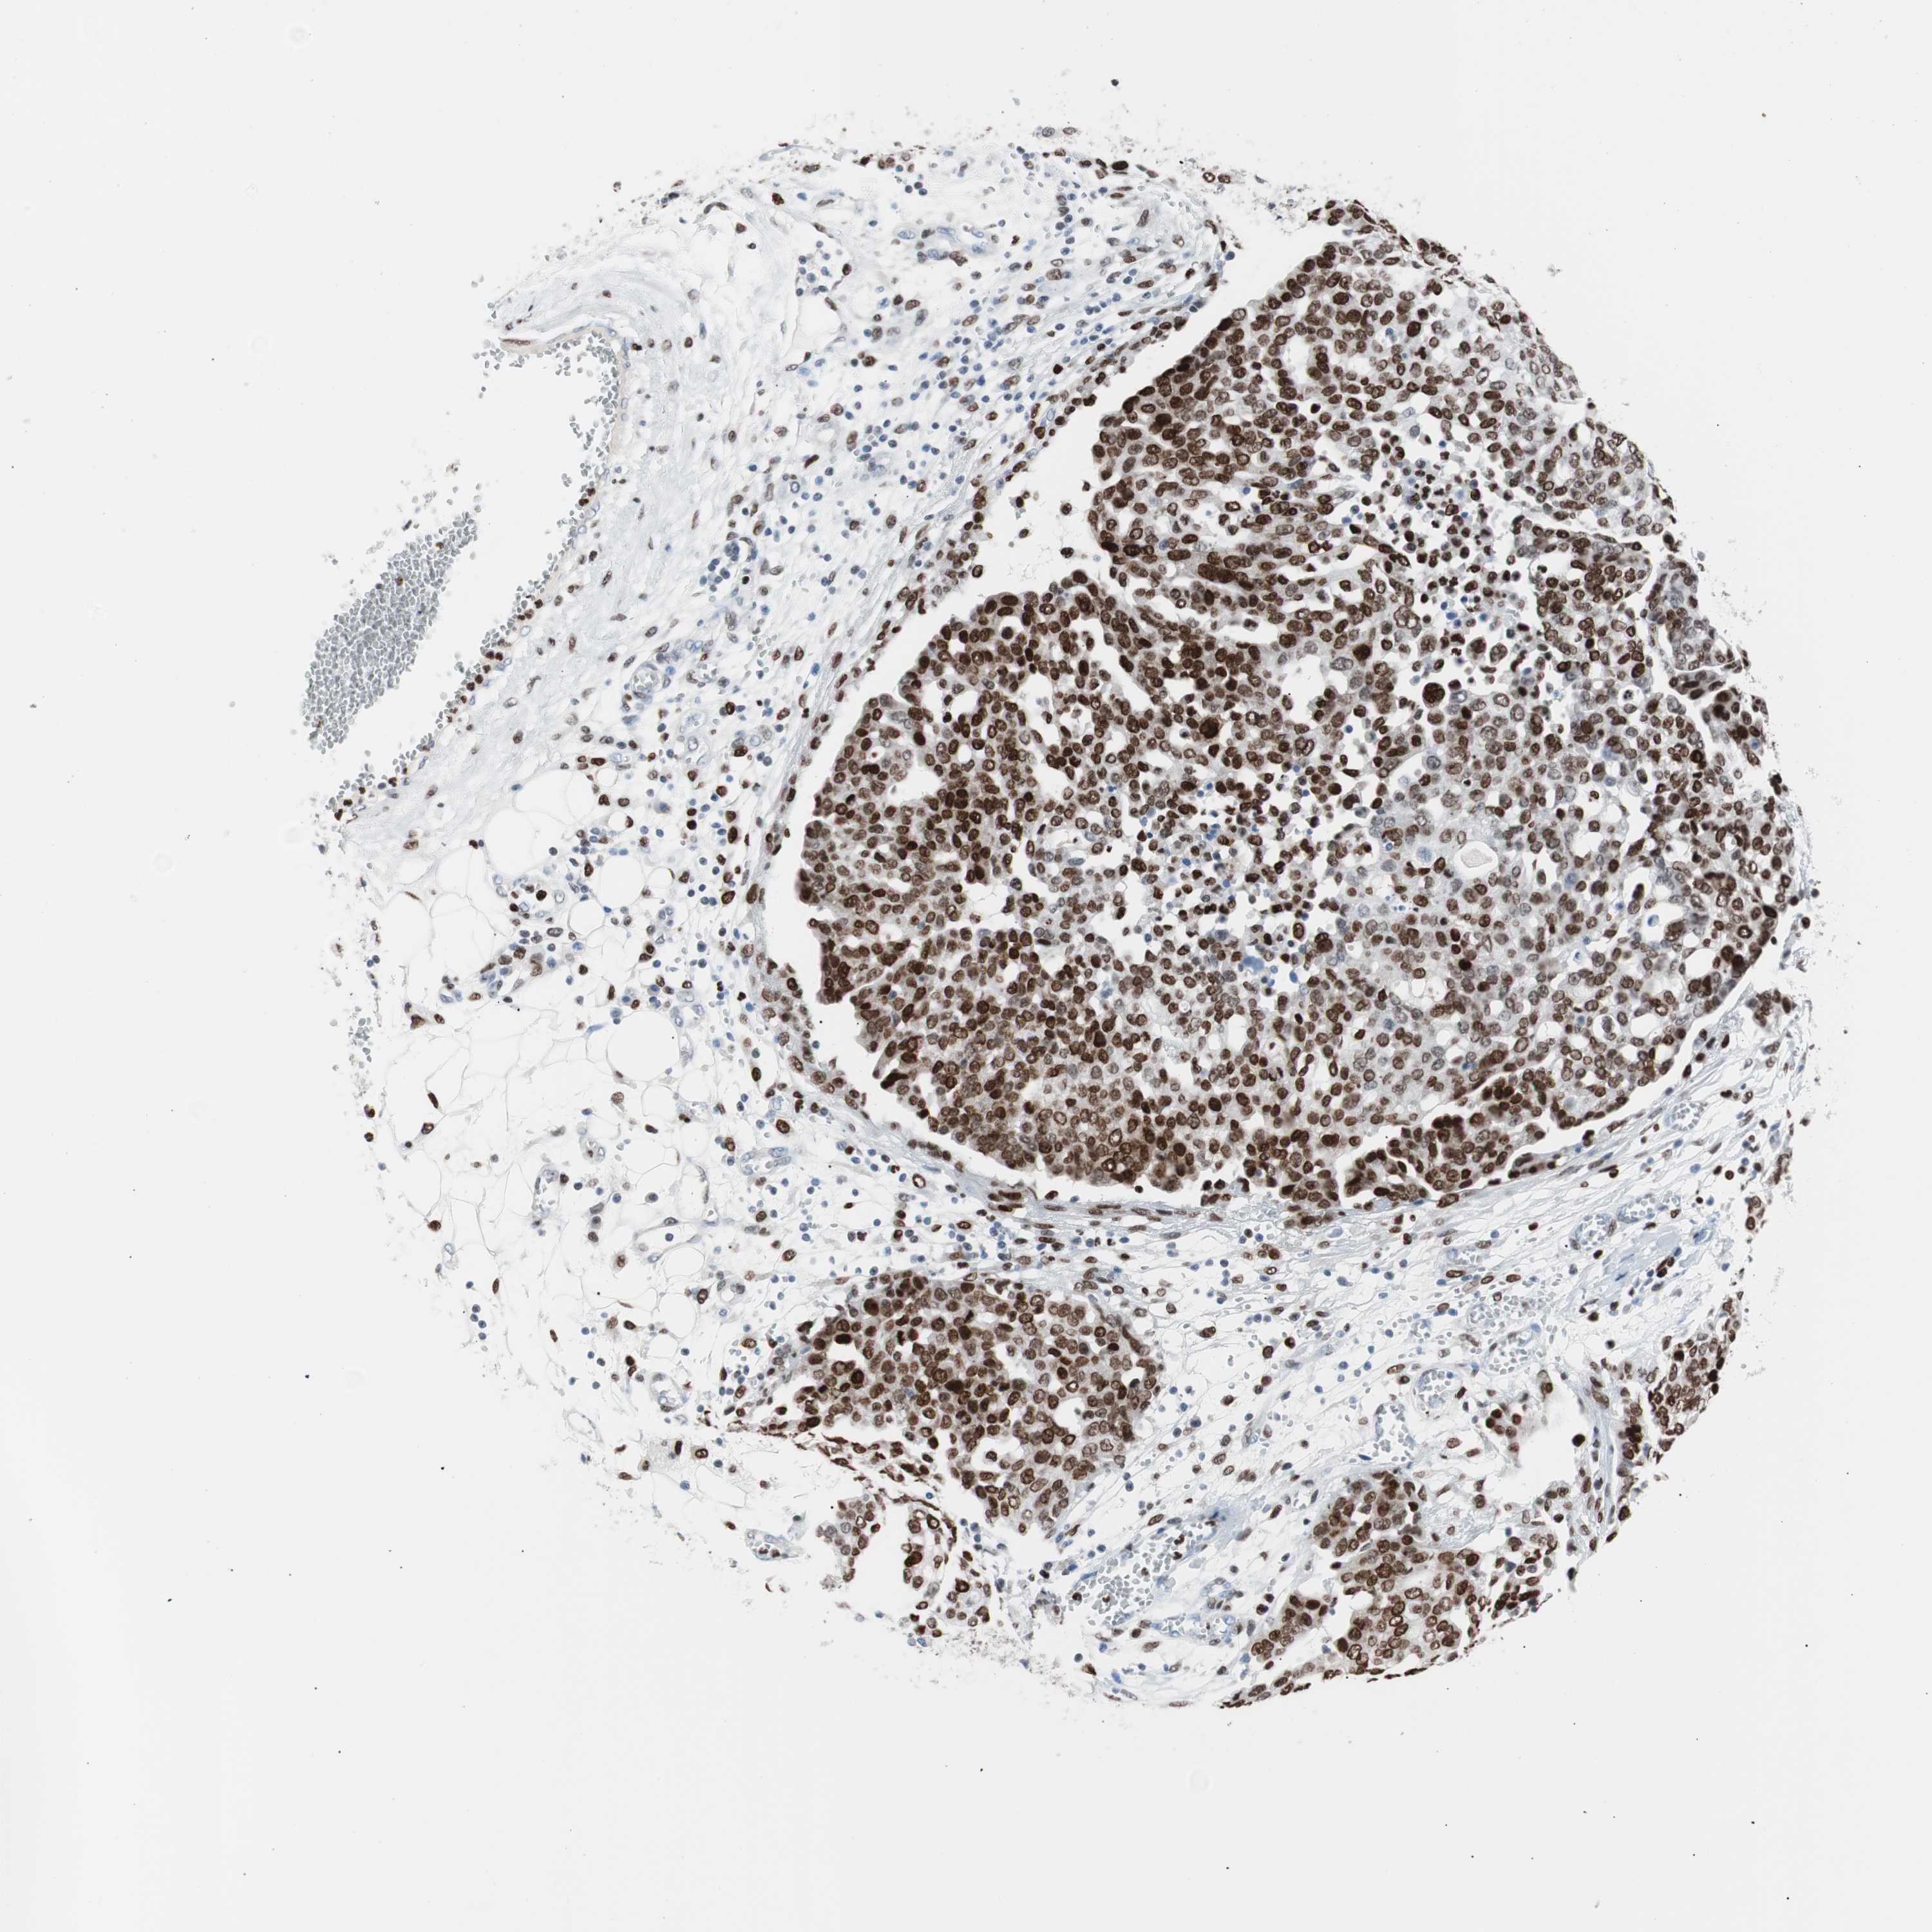

OVARIAN CANCER - Protein expressioni

A mouse-over function shows sample information and annotation data. Click on an image to view it in a full screen mode. Samples can be filtered based on level of antibody staining by selecting one or several of the following categories: high, medium, low and not detected. The assay and annotation is described here.

Note that samples used for immunohistochemistry by the Human Protein Atlas do not correspond to samples in the TCGA dataset.

Antibody stainingi

Antibody staining in the annotated cell types in the current human tissue is reported as not detected, low, medium, or high, based on conventional immunohistochemistry profiling in selected tissues. This score is based on the combination of the staining intensity and fraction of stained cells.

Each image is clickable and will lead to virtual microscopy that enables deeper exploration of all samples and also displays staining intensity scores, fraction scores and subcellular localization as well as patient and tissue information for each sample.

Antibody CAB004213

Staining

High

Medium

Low

Not detected

Intensity

Strong

Moderate

Weak

Negative

Quantity

>75%

75%-25%

<25%

None

Location

Nuclear

Cytoplasmic/membranous

Cytoplasmic/membranous,nuclear

Cystadenocarcinoma, serous, NOS

Carcinoma, endometroid

Carcinoma, NOS

Cystadenocarcinoma, mucinous, NOS